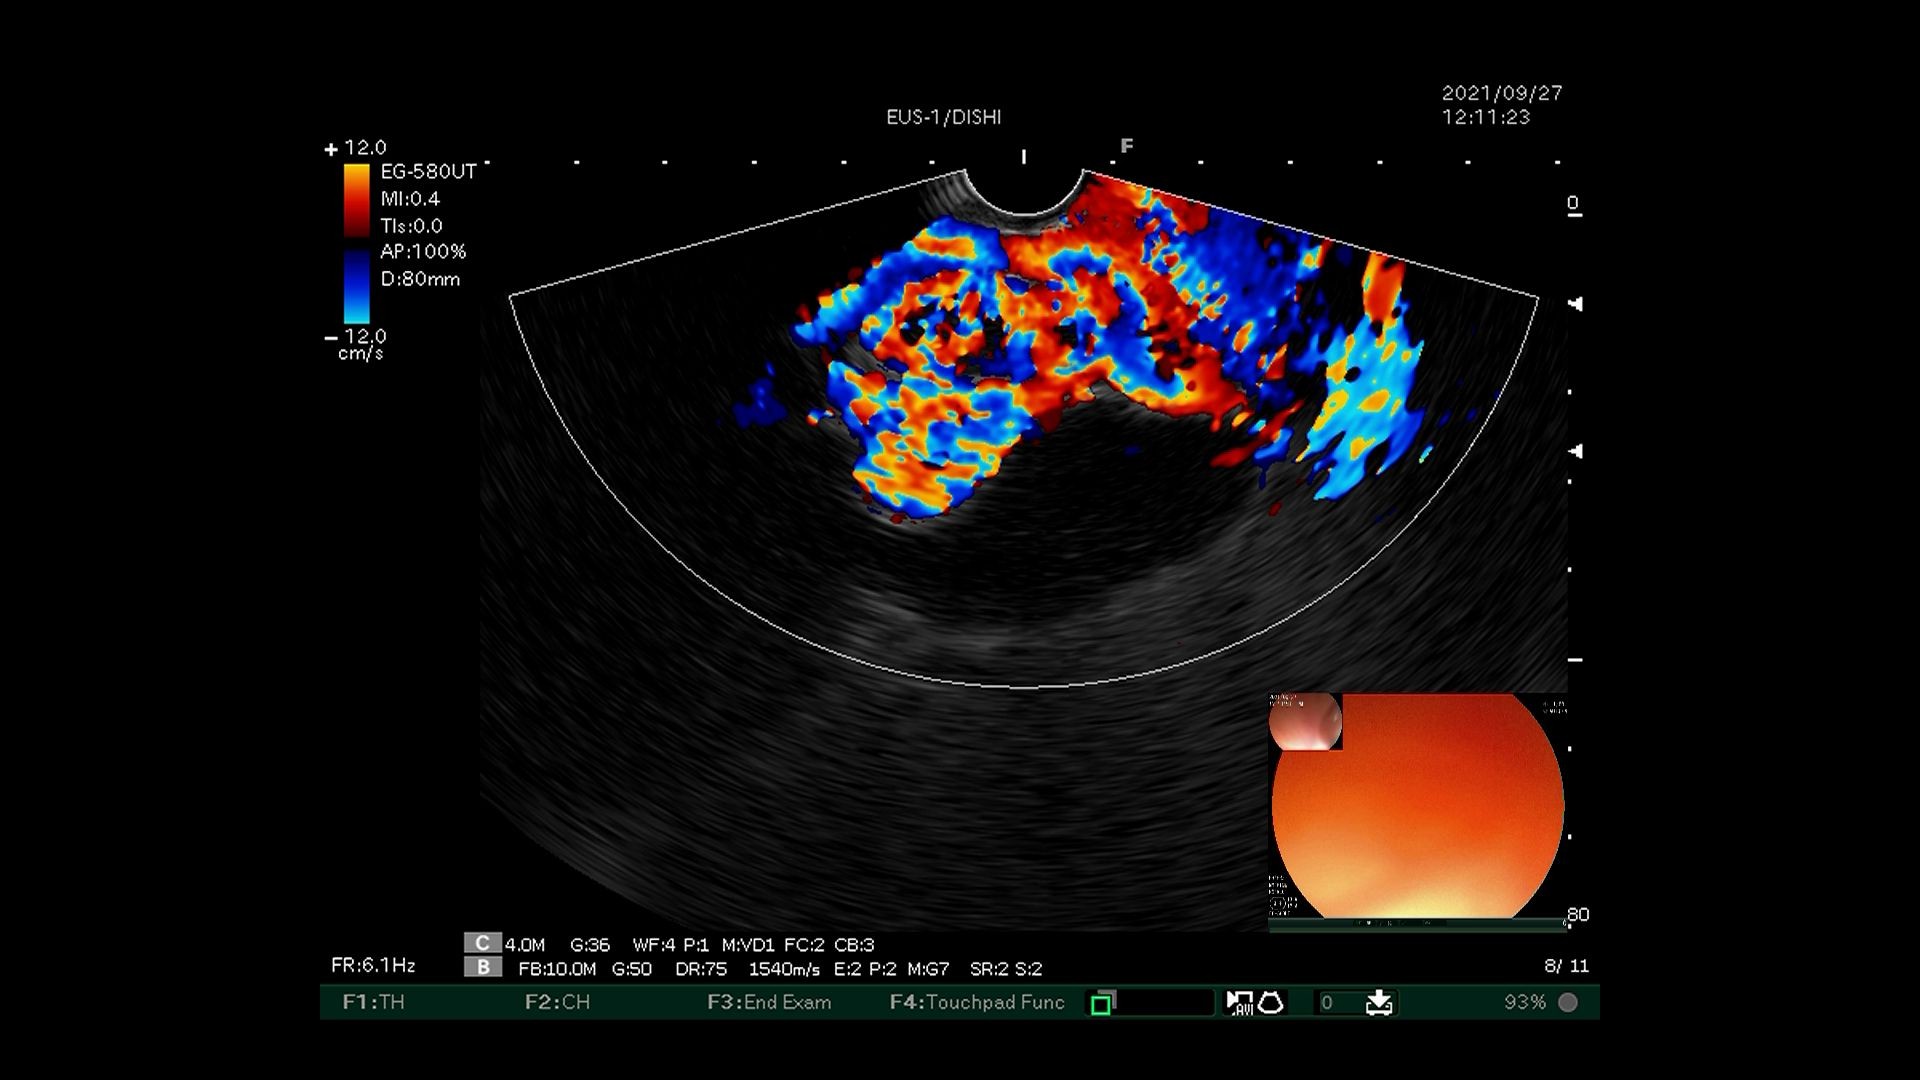

3)超声内镜下多普勒观察内部有丰富血流信号。